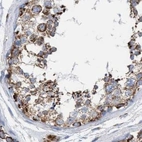

Immunohistochemistry analysis in human kidney and skin tissues using HPA022130 antibody. Corresponding ECI2 RNA-seq data are presented for the same tissues.